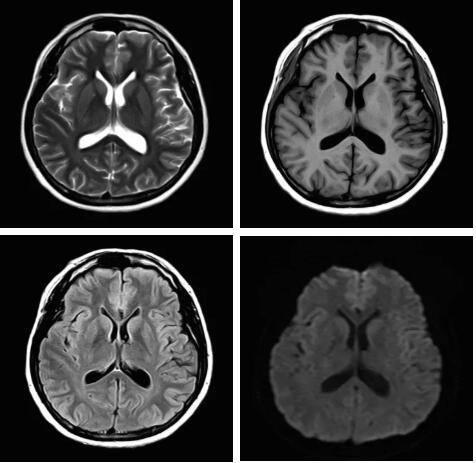

此技術(shù)主要用于神經(jīng)系統(tǒng)惡性腫瘤,以及其他腫瘤腦轉(zhuǎn)移瘤篩查。傳統(tǒng)情況下做腫瘤腦轉(zhuǎn)移篩查,很容易漏掉5mm以下小病灶,臨床發(fā)現(xiàn)后干預(yù)治療比較晚,要實(shí)現(xiàn)2mm高空間分辨率和超薄層全腦掃描在保證信噪比的情況下需要很長(zhǎng)時(shí)間大概十多分鐘,而且薄層增強(qiáng)序列顱內(nèi)血管呈高亮信號(hào),會(huì)干擾顱內(nèi)小病灶的觀察,血管和小病灶區(qū)分困難。佳能”螢火蟲”成像技術(shù)既可以實(shí)現(xiàn)高空間分辨率和超薄層(最薄可實(shí)現(xiàn)0.2mm)全腦掃描,掃描時(shí)間短,2-3分鐘即可實(shí)現(xiàn)全腦3D掃描,同時(shí)避免了血管高亮信號(hào)的干擾,對(duì)顱內(nèi)原發(fā)或繼發(fā)的微小腫瘤檢查有重大意義。“螢火蟲”成像技術(shù)具有磁敏感效應(yīng),對(duì)于亞急性血敏感敏感,可以區(qū)分出血和強(qiáng)化的腫瘤。